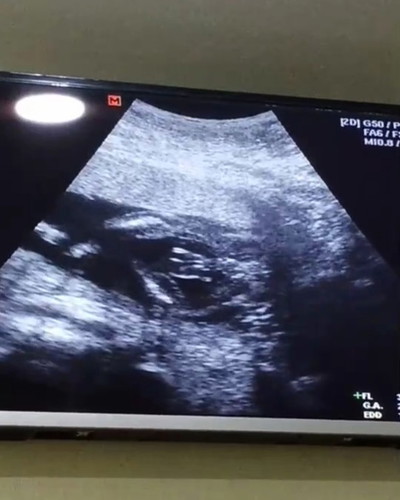

ทีมตุลาจ้า บ้านไหนได้ผู้ชายสมใจคุณพ่อบ้างไหมค่ะ ? คุณหมอบอกมาเป็นพวงเลย 19w+6d โตเกินอีกตังหาก

20 week 6 Day ค่ะ บ้านนี้ก็ผช.เหมือนกันเลย ดิ้นเก่ง เตะเก่งมากค่ะ